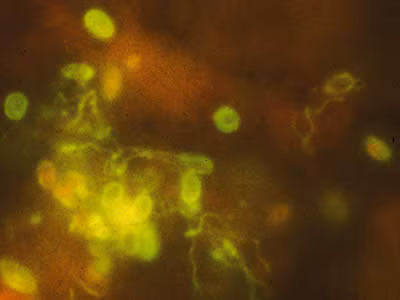

Immunofluorescence Assays (IFA)

IFAs are available for microsporidia using monoclonal and/or polyclonal antibodies.